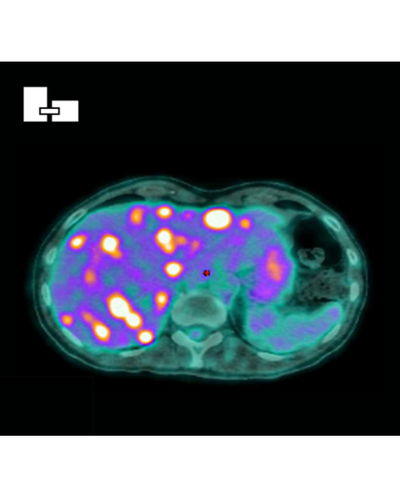

- Une avancée majeure dans le traitement du cancer anal grâce à une stratégie combinant immunothérapie et radiothérapie adaptative

Une avancée majeure dans le traitement du cancer anal grâce à une stratégie combinant immunothérapie et radiothérapie adaptative

L’équipe de cancérologie digestive du CHU de Besançon / IRFC Franche-Comté vient de publier dans The Lancet Oncology une étude majeure qui pourrait transformer la prise en charge du carcinome épidermoïde du canal anal localement avancé.

L’essai INTERACT-ION, porté par le Pr Stefano Kim, a évalué une stratégie combinant :

- une immunothérapie (ezabenlimab),

- une chimiothérapie d’induction (combinaison DCF),

- puis une radiothérapie adaptative, ciblant uniquement les ganglions atteints.

Cette approche vise à renforcer la réponse immunitaire contre la tumeur tout en limitant la toxicité du traitement.

Menée auprès de 55 patients atteints de cancer du canal anal de stade 3 dans dix hôpitaux français, l’étude a montré :

- 78 % de réponses complètes à 40 semaines,

- plus de 80 % de survie sans progression à deux ans,

- et une tolérance globale satisfaisante, avec moins d’effets secondaires graves que la prise en charge conventionnelle.